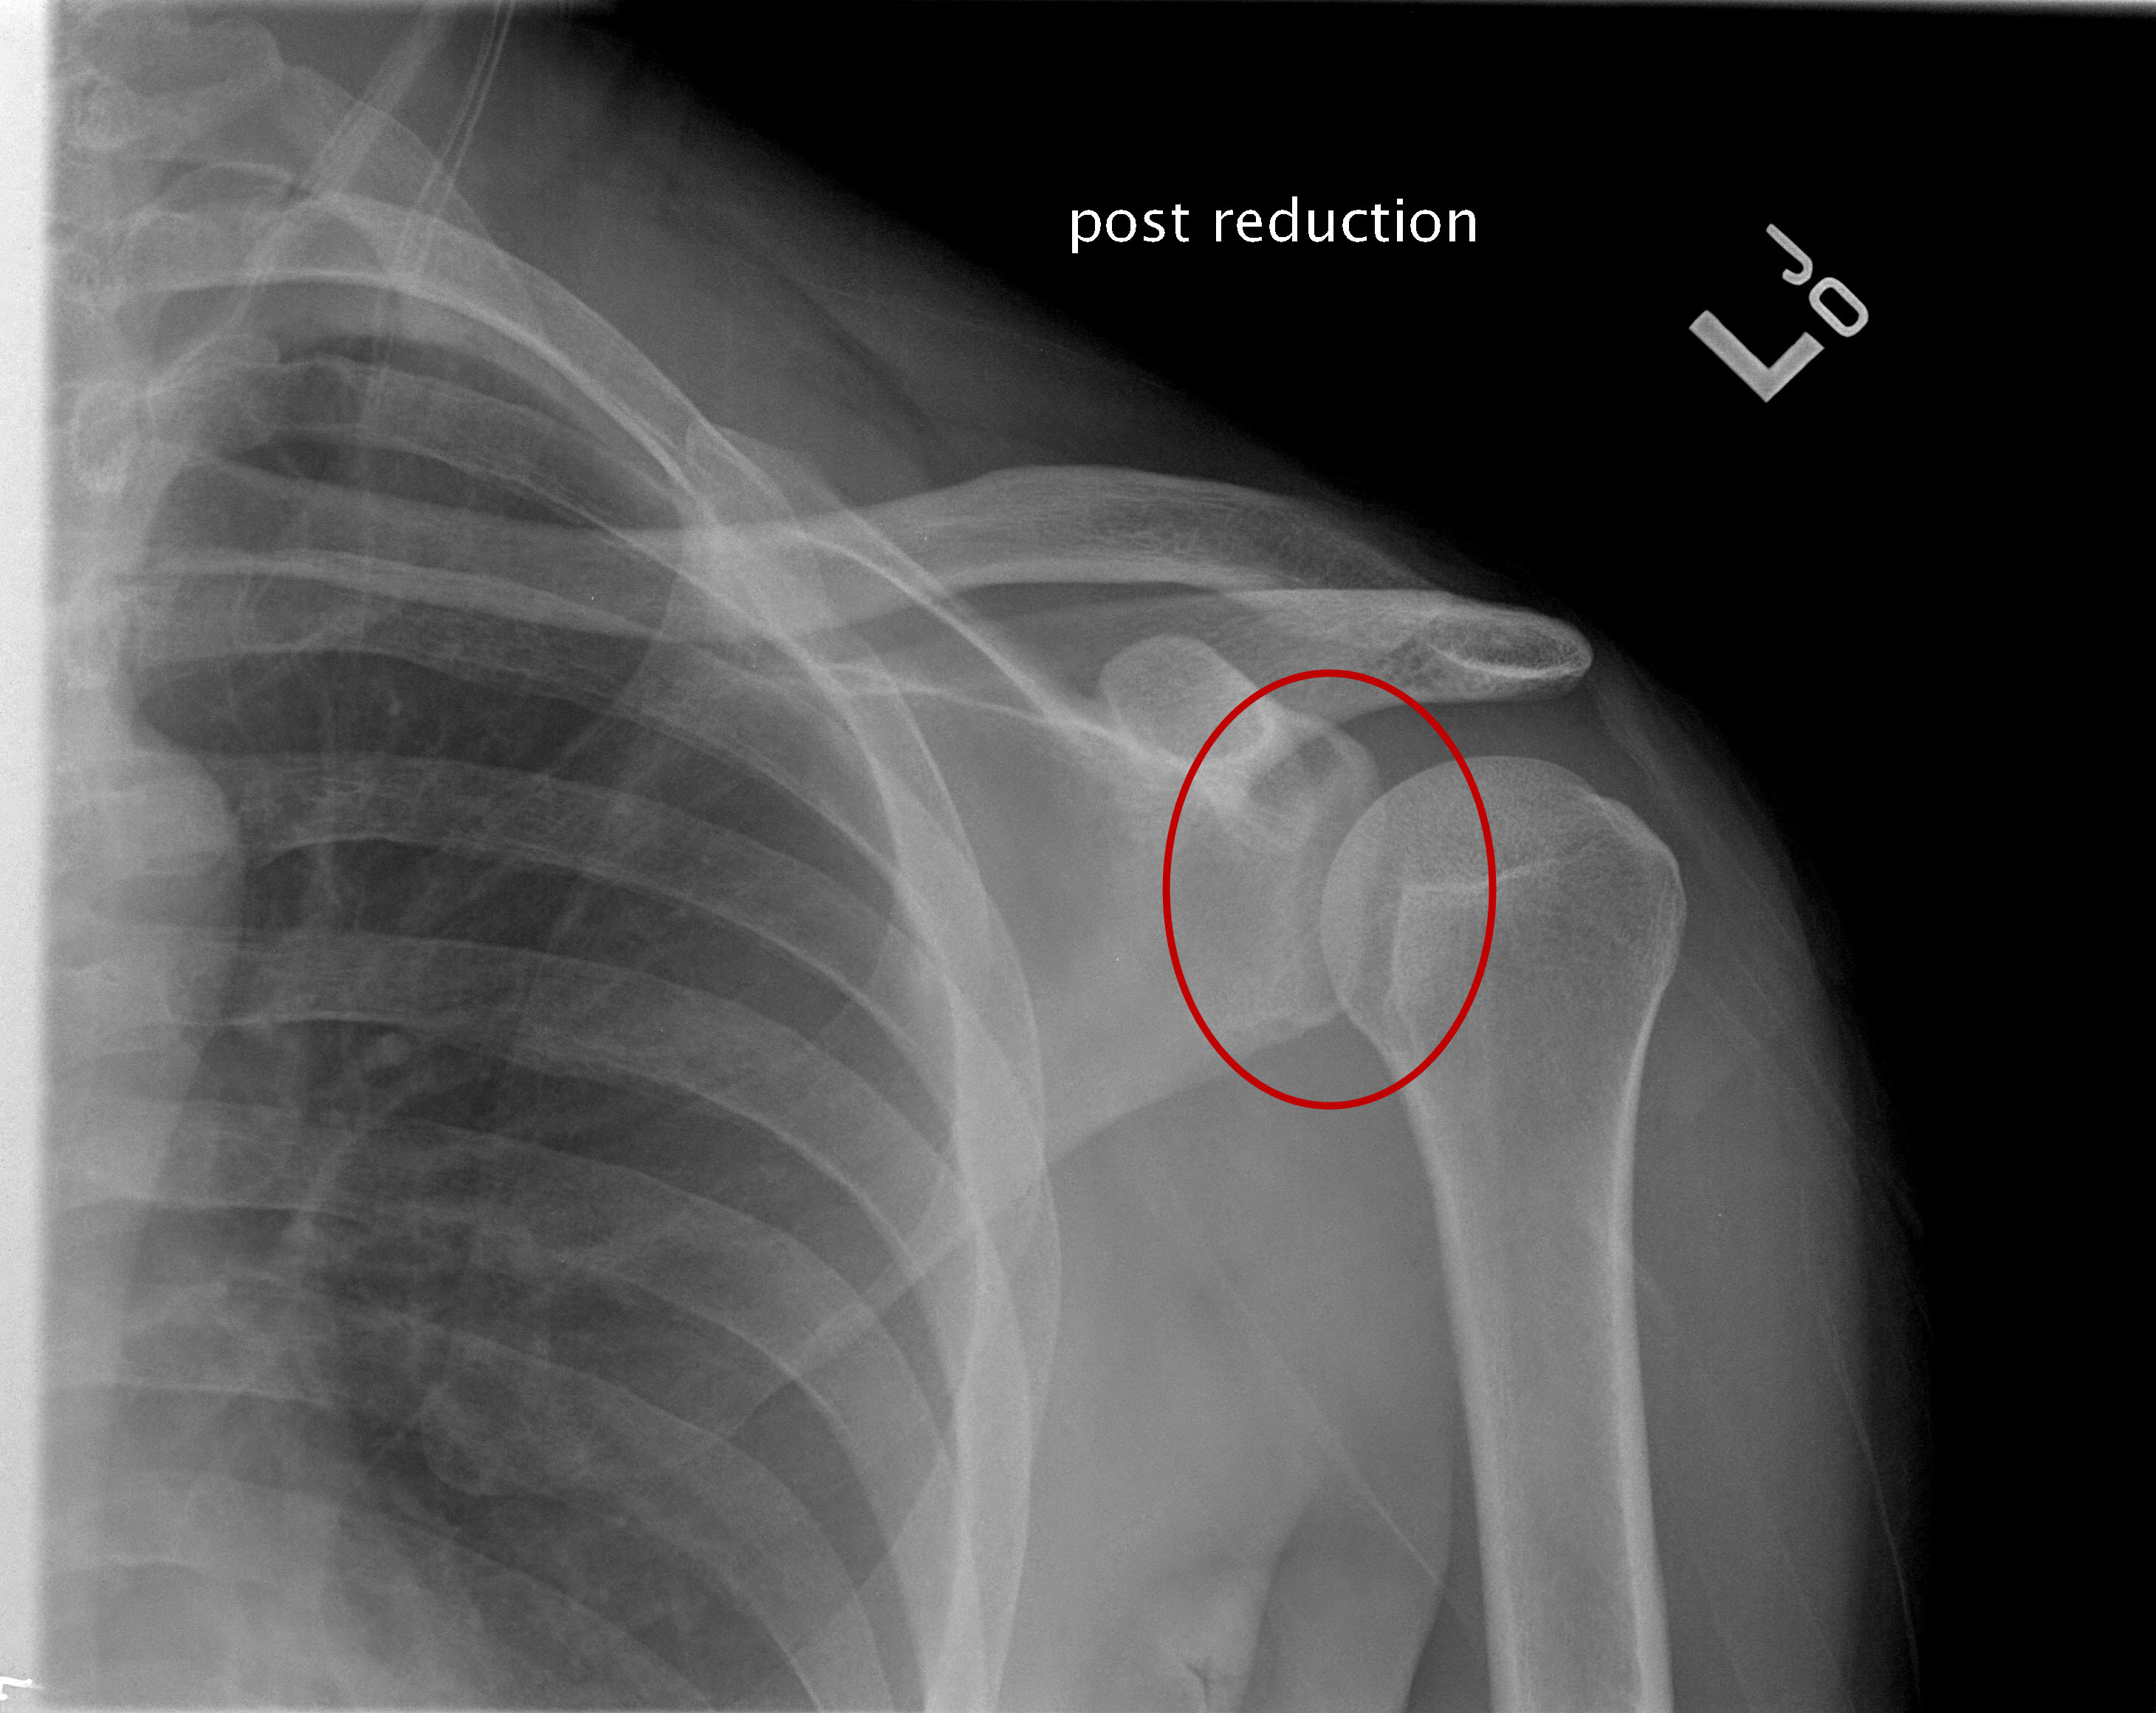

Immediate Treatment: Reduction

The first step in treating a dislocated shoulder is reduction, which involves moving the humeral head back into the socket. This procedure should be performed by a trained medical professional to avoid further injury.

X-Ray Imaging (All Images in Gallery Below):

- For any suspected dislocation, obtain 3 views: AP, Scapula Y, and Axillary (see Approach to Traumatic Shoulder Pain for normal X-ray anatomy)

- Anterior Dislocation

- AP View: Humeral head dislocated anteriorly and rests under the coracoid process

- Scapula Y View: Scapula Y view: humeral head displaced medially (to the right) of the scapula

- Axillary view: Humeral head displaced anteriorly in front of the coracoid process